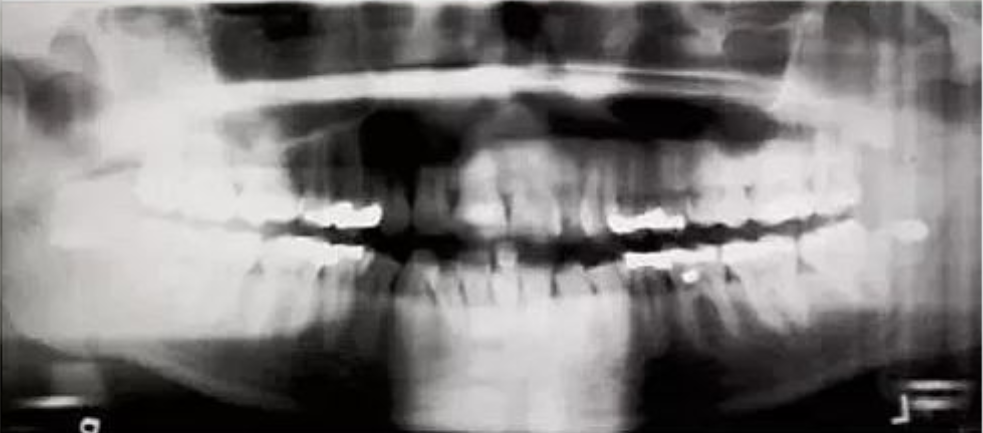

八、影像倾斜,一侧髁骨明显高于另一侧

【失误原因】

中矢激光束未对准,患者倾斜。

【解决方法】

将中矢激光束与鼻根中线进行对准。